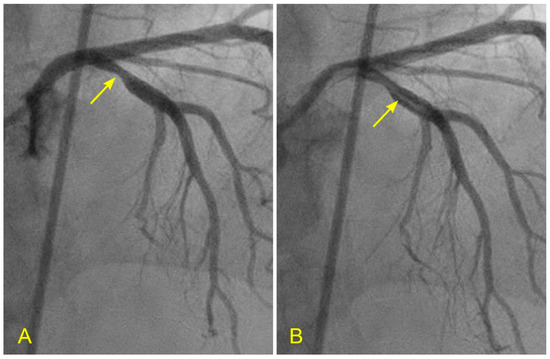

Figure 6. (A,B) Timing of systole and diastole in the left anterior oblique (LAO) caudal (spider) view. These are the two consecutive images of the left main artery (LM) in the spider view. They are separated by 0.06 s (recorded at 15 frames per second). (A) In this view, the ostium of the left anterior descending artery (LAD) is seen well, so the flow through it would be imaged well (arrow). (B). In this view, the contrast in black color is visibly ejected from the aortic root and the coronary sinus into the ascending aorta (arrow), with black contrast in the ascending aorta (arrowhead). These features help to time and differentiate between the flow in the coronary artery during systole and diastole. - The left anterior oblique (LAO) cranial view for the proximal segment (Figure 7A,B)

Figure 7. (A,B) Laminar flow across a lesion in the left anterior oblique (LAO) cranial view, which is important for the presence of antegrade laminar flow or turbulent retrograde flow. (A) In this anterior–posterior (AP) cranial view, the proximal segment of the left anterior descending artery (LAD) was completely filled with contrast. There was a moderate lesion (arrow). (B) In this view, the blood, in white, was seen to cross the stenotic segment in laminar flow (arrow) over a background of black contrast. Under the protective effect of laminar flow, the lesion stayed stable, not progressing to acute coronary syndrome while the patient was on optimal dose of beta-blockers and statin. - The anteroposterior (AP) cranial view for the proximal and mid-segments (Figure 8A,B)

Figure 8. (A,B) Lesion in the proximal and mid left anterior descending artery (LAD) in the anteroposterior (AP) cranial view. This view is essential for searching for antegrade laminar or turbulent retrograde flow. (A) In this picture, there is a critical narrowing in the proximal segment of the LAD, proximal to the origin of a moderate-size diagonal (arrow). In our research protocol, for a lesion at this location, we would ask why and how the lesion formed in the proximal LAD, proximal to the ostium of the diagonal and the main branch (and not at other locations). Which fluid mechanics mechanism(s) was (were) responsible for forming lesions at this location? Could it have been due to retrograde flow from the diagonal and distal LAD? (B). This picture shows a critical narrowing in the mid-segment of the LAD (arrow) and the ostium of the moderate-size diagonal (arrowhead). In our research protocol, we would ask the same questions about the formation of lesions at these two locations.